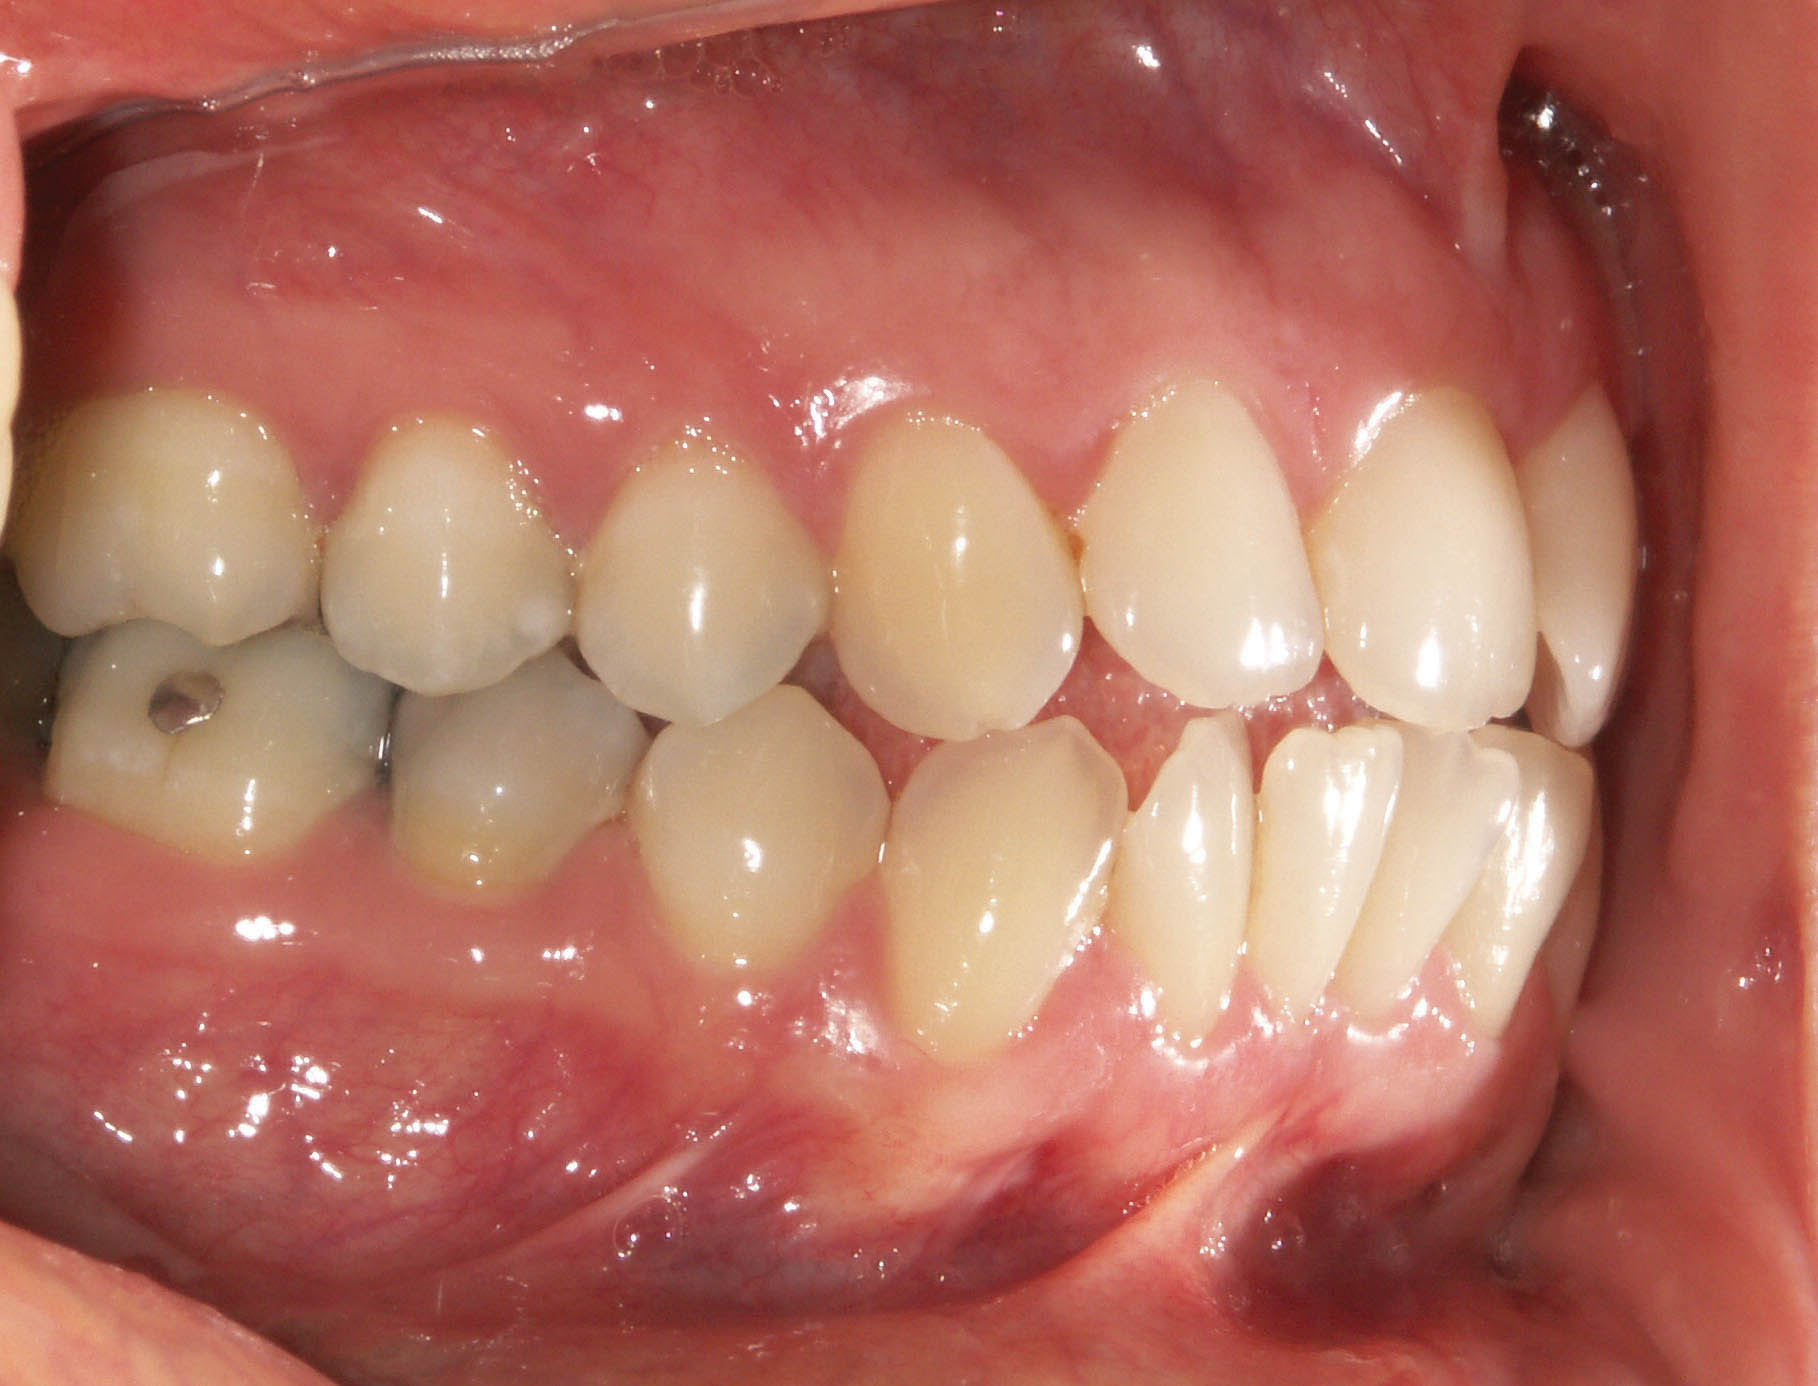

شکل 114-2: 2mm کلاسII در سمت راست

وقتی 2mm کلاسII باشد (شکل 114-2) اگر پرمولرهای بالا را فقط بخاطر 2mm کلاسII بودن بکشید آن موقع برای رسیدن به یک کاسپ کامل کلاسII، مولرهای شما باید 5mm حرکت مزیالی بکنند که از لحاظ مکانیکی کاری بسیار سخت است. بیماران هم شکایتی از اورجت زیاد ندارند چون 2mm کلاسII اورجت زیادی برای آنها درست نمیکند. این بیماران را مانند بیماران کلاسI (منتهی حد مزیالی آن) قبول میکنیم و چون بنا برغیرکشیدنی بودن فک پائین است، لذا بالا را هم غیرکشیدنی درنظر میگیریم و ارتودنسی را تمام میکنیم (شکل 115-2).